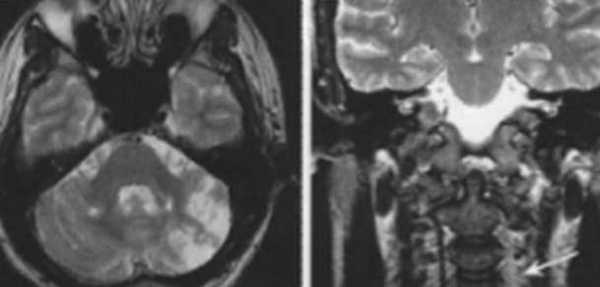

Характерным проявлением ДЭП на МР-томограммах является наличие множественных очагов глиоза.

В белом веществе левой лобной и обеих теменных долей, преимущественно субкортикально, выявлены множественные мелкие очаги хронической ишемии (большинство локализованных в бассейне правой средней мозговой артерии).

Проявлением хронической ишемии является также развитие выраженных дистрофических изменений белого вещества паравентрикулярной локализации - лейкоареоз.

Выраженные дистрофические изменения белого вещества паравентрикулярной локализации - лейкоареоз.

Сочетание мультифокальных очаговых изменений с диффузной кортикальной церебральной атрофией.